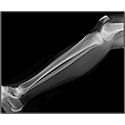

LOWER LIMB

Interactive Radiology